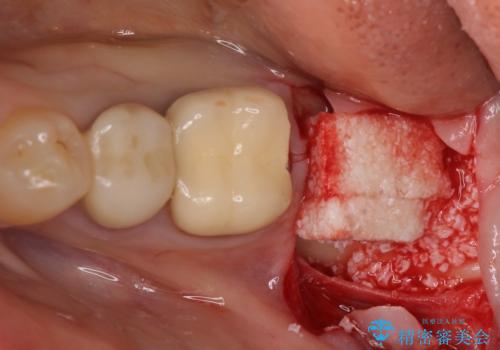

インプラント埋入にあたり、歯槽骨での炎症が広範囲であったことから、事前に骨造成を行いました。

歯槽骨の高さや幅を回復することができ、望ましい位置にインプラントを埋入することができました。